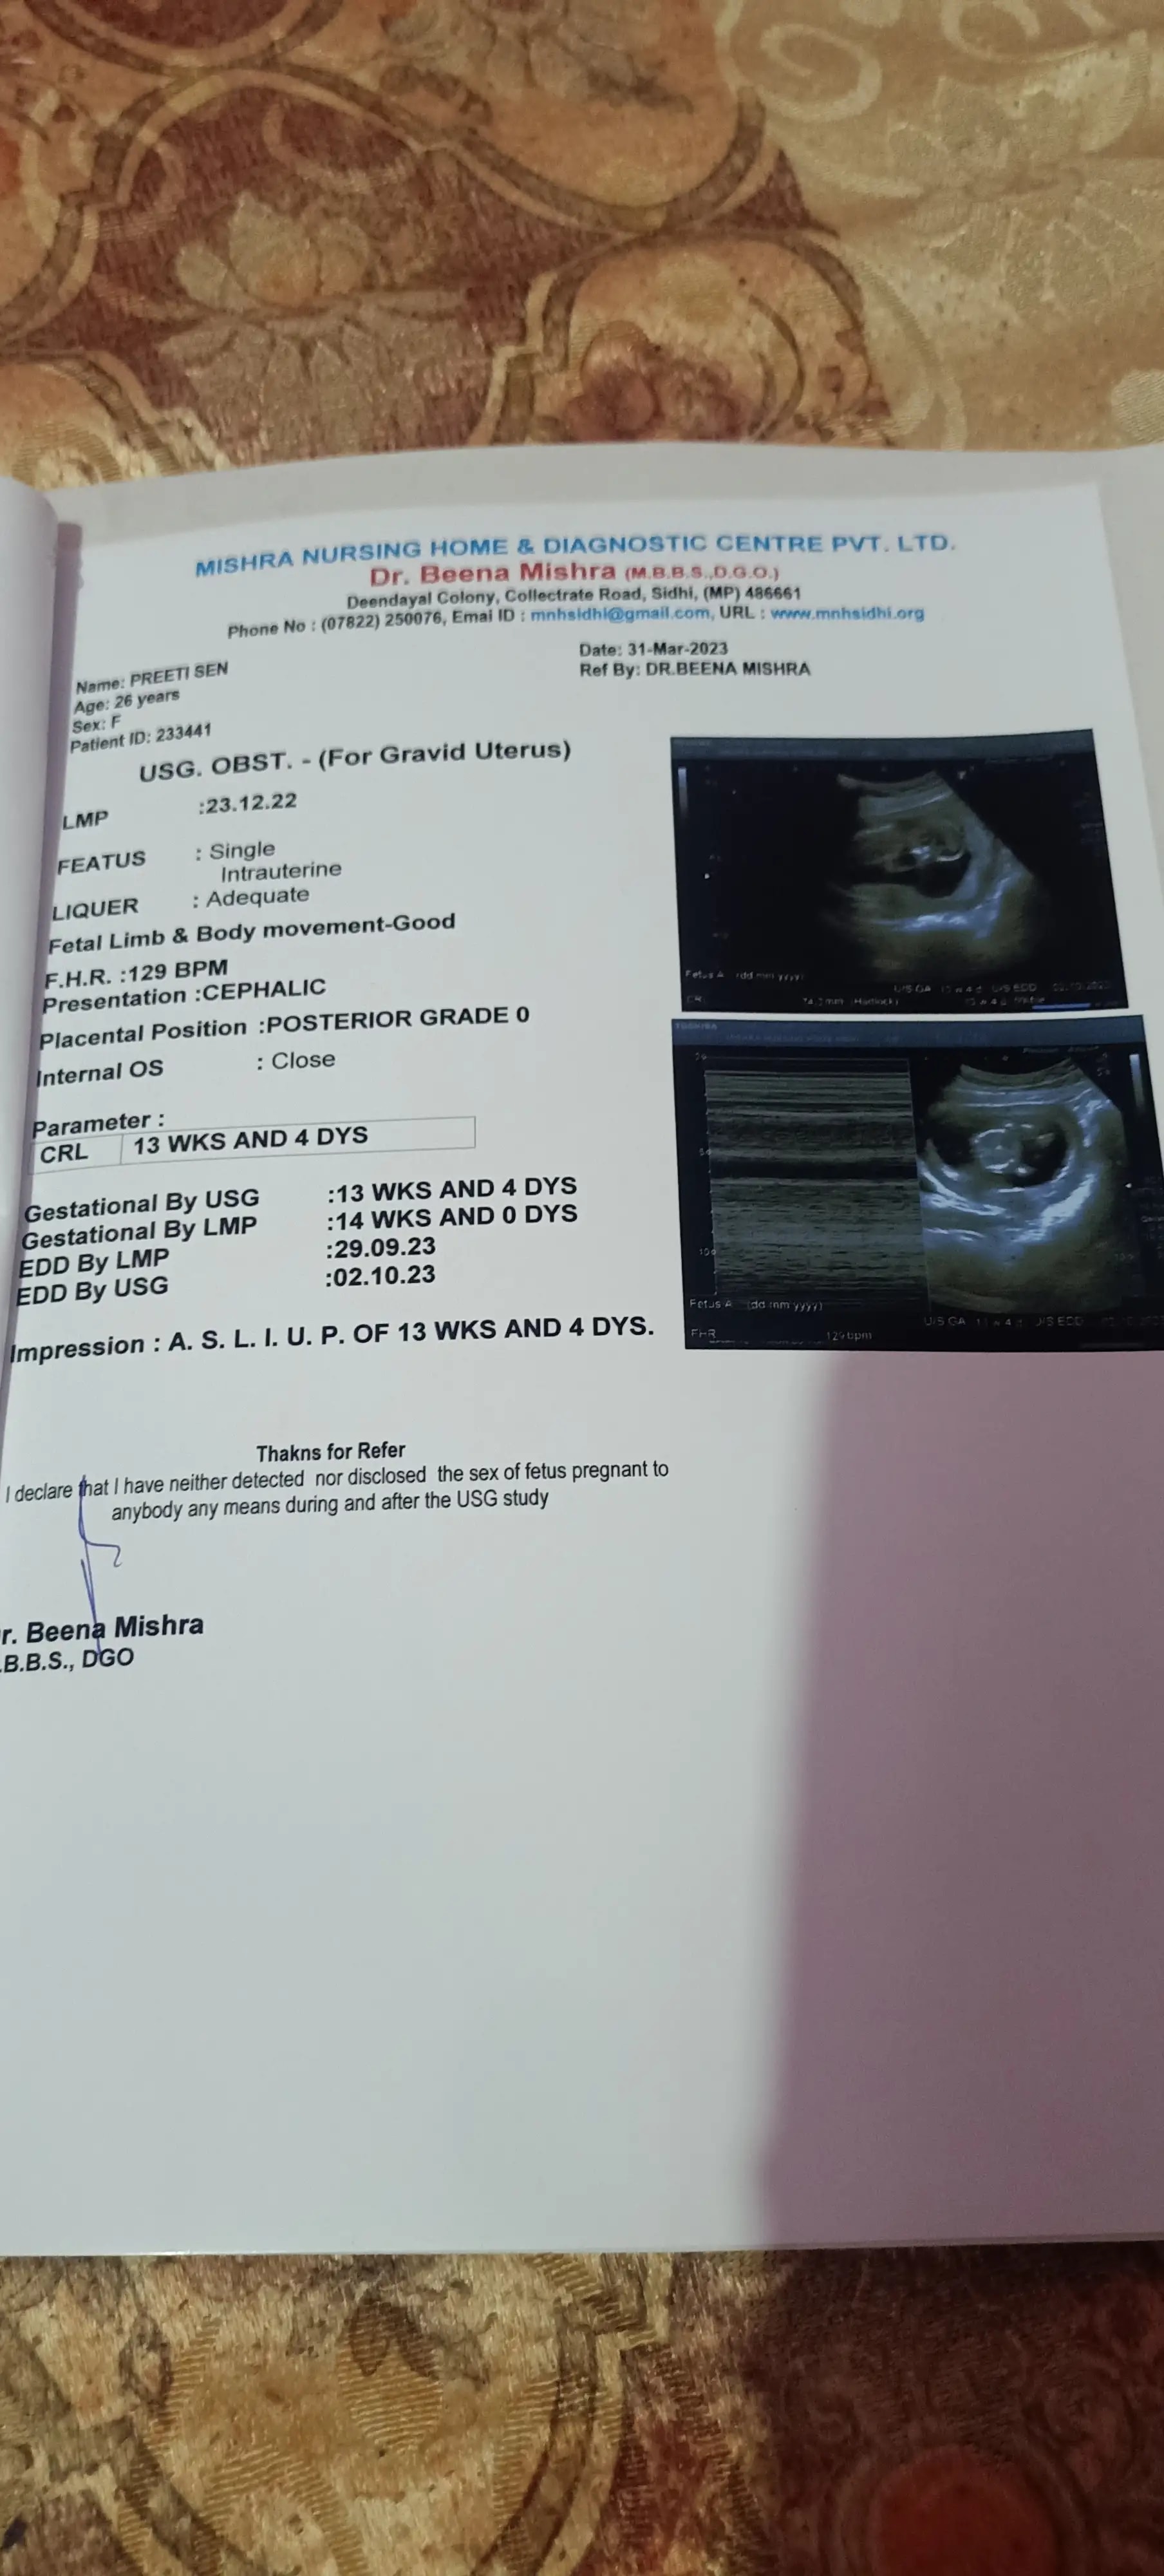

Pregnancy